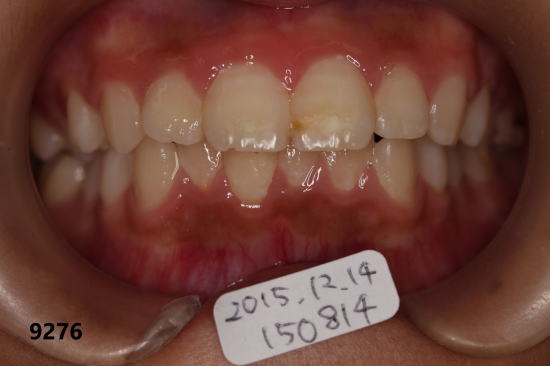

| 2016年11月17日:約1年3ヶ月後 緑の矢印の部分はほぼ完璧にむし歯(白濁)が治癒 |

フッ素洗口だけで歯を削らず、初期のむし歯は奥歯を含めて元の状態に 戻っています。 歯を削って人工物を入れるとその人工物は経年的に劣化します。 ですから、初期のむし歯は削らず、フッ素洗口で修復した方が賢明です。 むし歯があっても元に戻る状態なら、この人は今後、この状態を維持す ればむし歯になる事はありません。 |